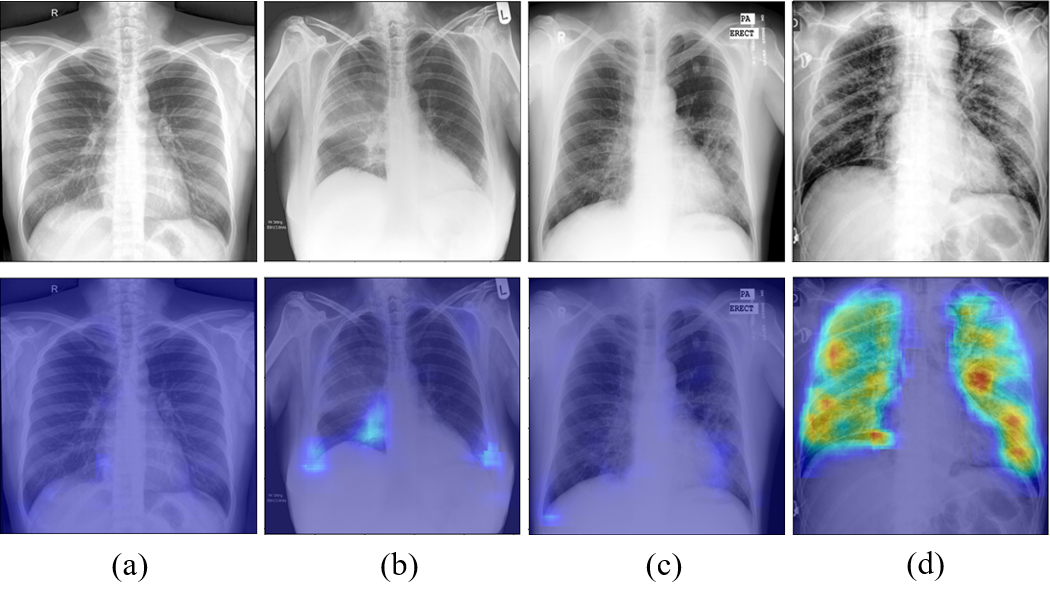

Fig. 7 and Fig. 8 illustrate the examples of visualization of saliency map. As shown in Fig. 7(a), the existing Grad-CAM method for global approach showed the limitation that it only focuses on the broad main lesion so that it cannot properly differentiate multifocal lesions within the image. On the other hand, with the probabilistic Grad-CAM, multifocal GGOs and consolidations were visualized effectively by our local patch-based approach as shown in Fig. 7(c), which was in consistent with the findings reported by clinical experts. In particular, when we compute the probabilistic Grad-CAM for the COVID-19 class using patient images from various classes (i.e., normal, bacterial, TB, and COVID-19), a noticeable activation map was observed only in the COVID-19 patient data set, whereas almost no activations were observed in patients with other diseases and conditions as shown in Fig. 8. These results strongly support our claim that the probabilistic Grad-CAM saliency map from our local patch-based approach is more intuitive and interpretable compared to the existing methods.